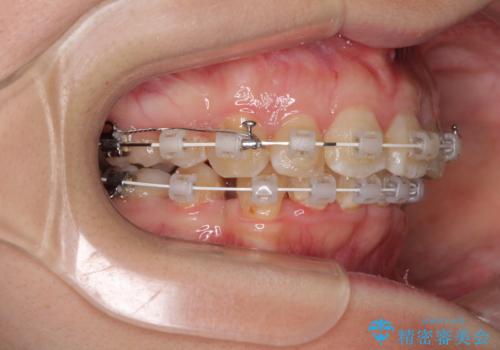

- 矯正装置

- 審美装置

咬み合わせが深く、咬合力強いため、補助装置を使用しながら積極的に口元を下げることとしました。

矯正治療終了近くに九州へ引っ越すことになってしまい、なかなか来院することができなくなったため、引っ越してから1年以上の期間が必要となってしまいました。